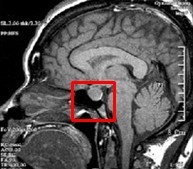

성장호르몬은 뇌, 그중에서도 뇌하수체에서 분비됩니다. 이 질환은 뇌하수체나 그 주변에 생긴 병변으로 인해 기능에 문제가 발생하여 성장호르몬 분비가 결핍됨으로써 발생합니다. 출생 시 머리의 충격이나 유전적인 결함, 뇌하수체 종양이나 시상하부의 종양이 원인이 될 수 있습니다. 또한 후천적인 뇌 손상, 뇌염, 뇌막염의 후유증, 염증성 질환, 방사선 치료에 의한 손상 등이 원인이 될 수 있습니다.

뇌의 뇌하수체 MRI 사진